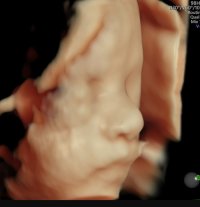

Det er veldig forståelig. Gleder meg også veldig til å ha toul overstått, og kanskje aller mest til jeg kan begynne å kjenne liv selvSamme her! Turte liksom ikke tro på at det kunne være noe annet enn BO før jeg var på tidlig-tidlig UL 7+1. Nå er det MA som er frykten selv om jeg aldri har opplevd det... Det skal bli godt å bli ferdig med TOULom 3 uker og kanskje få litt mer ro!

12+0 i dag!